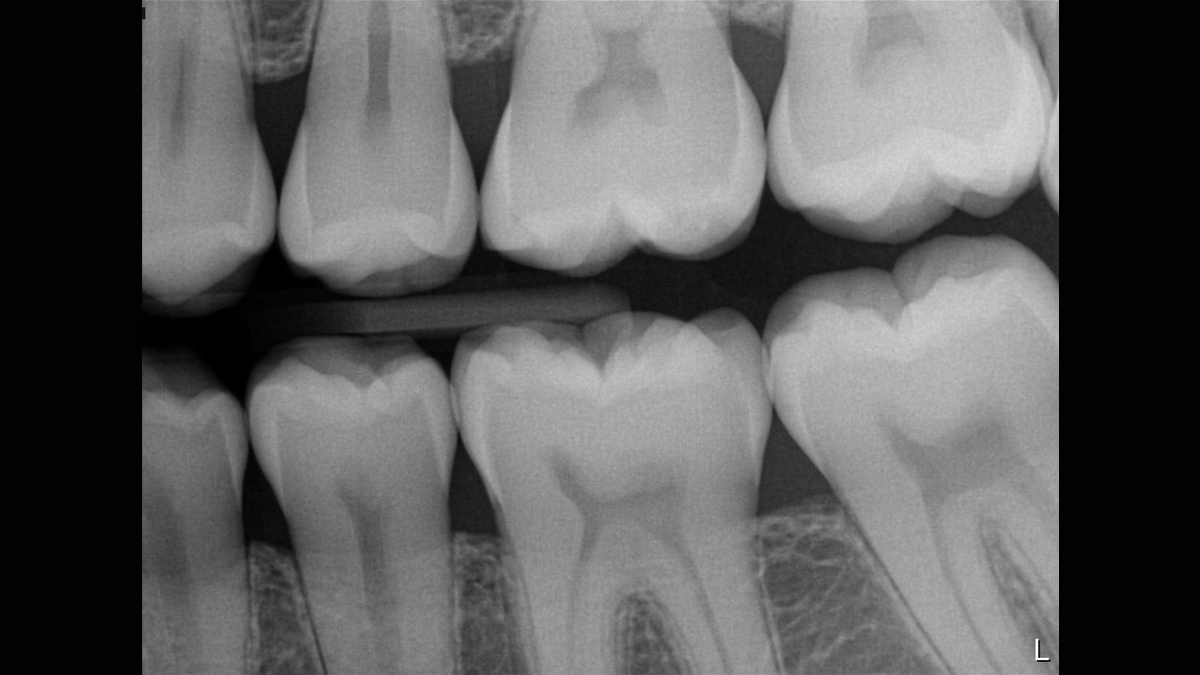

Excellent Image Quality

Xios XG Supreme provides a theoretical resolution of 33 lp/mm and a 15 μm pixel size.

Working with Xios XG Supreme: Filtering enhancements

With Xios XG Supreme sensors you have the option of five different filtering options: General Dentistry, Endodontics, Periodontics, Restorative and Hygiene. These clinically specific views are designed to optimize your diagnosis, enhancing the image to suit your needs.

Gallery of Sample Images